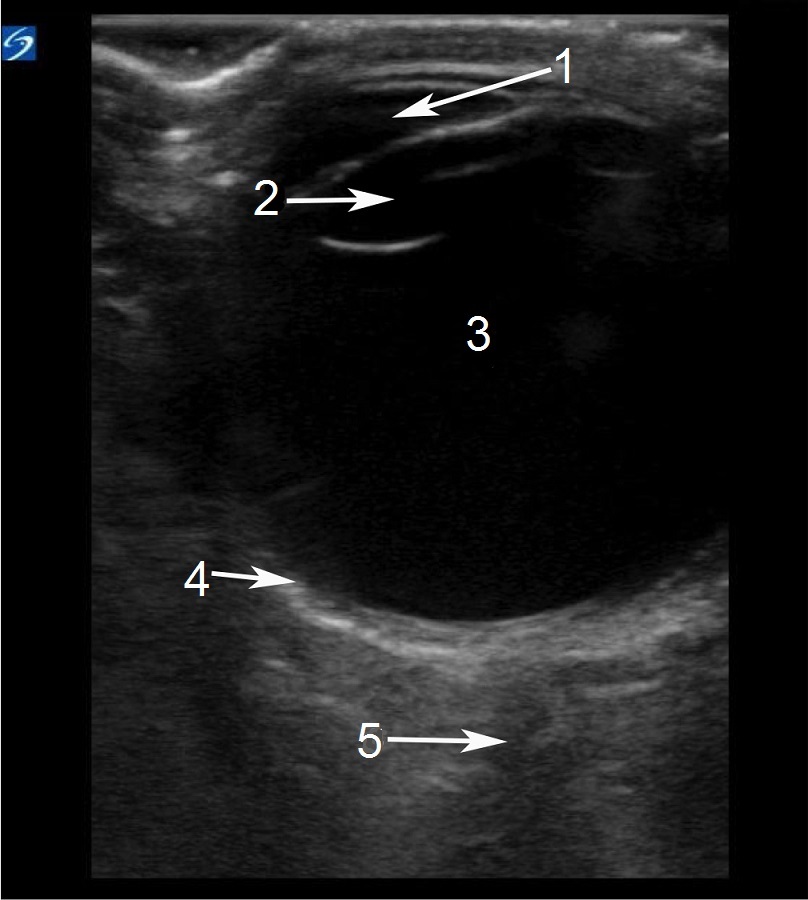

眼部正常解剖结构 2 图像

前房

晶状体

玻璃体

视网膜

视神经